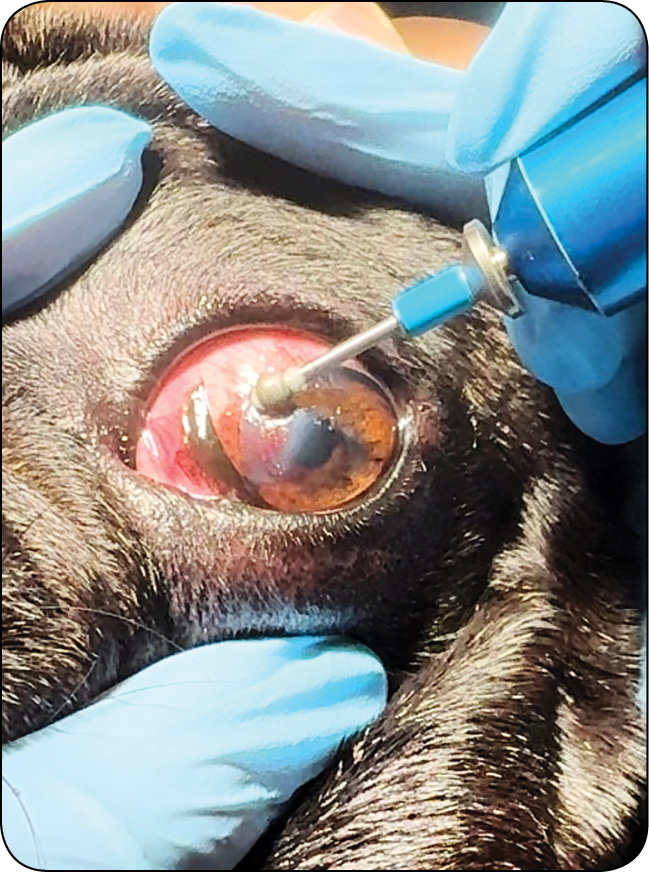

Owrzodzenia rogówki u małych zwierząt – klasyfikacja, diagnostyka i leczenie

Leczenie wspomagające